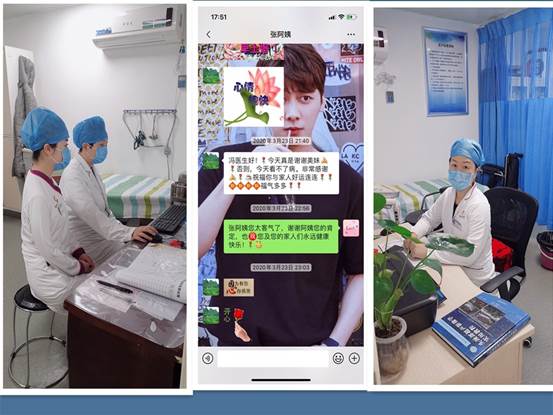

为做好疫情期间患者服务,减少人员聚集,从病人角度出发,合理安排候诊次序,得到了病人的一致好评,并且还收获了病人微信感谢短信.

作者:冯云 谢欣欣